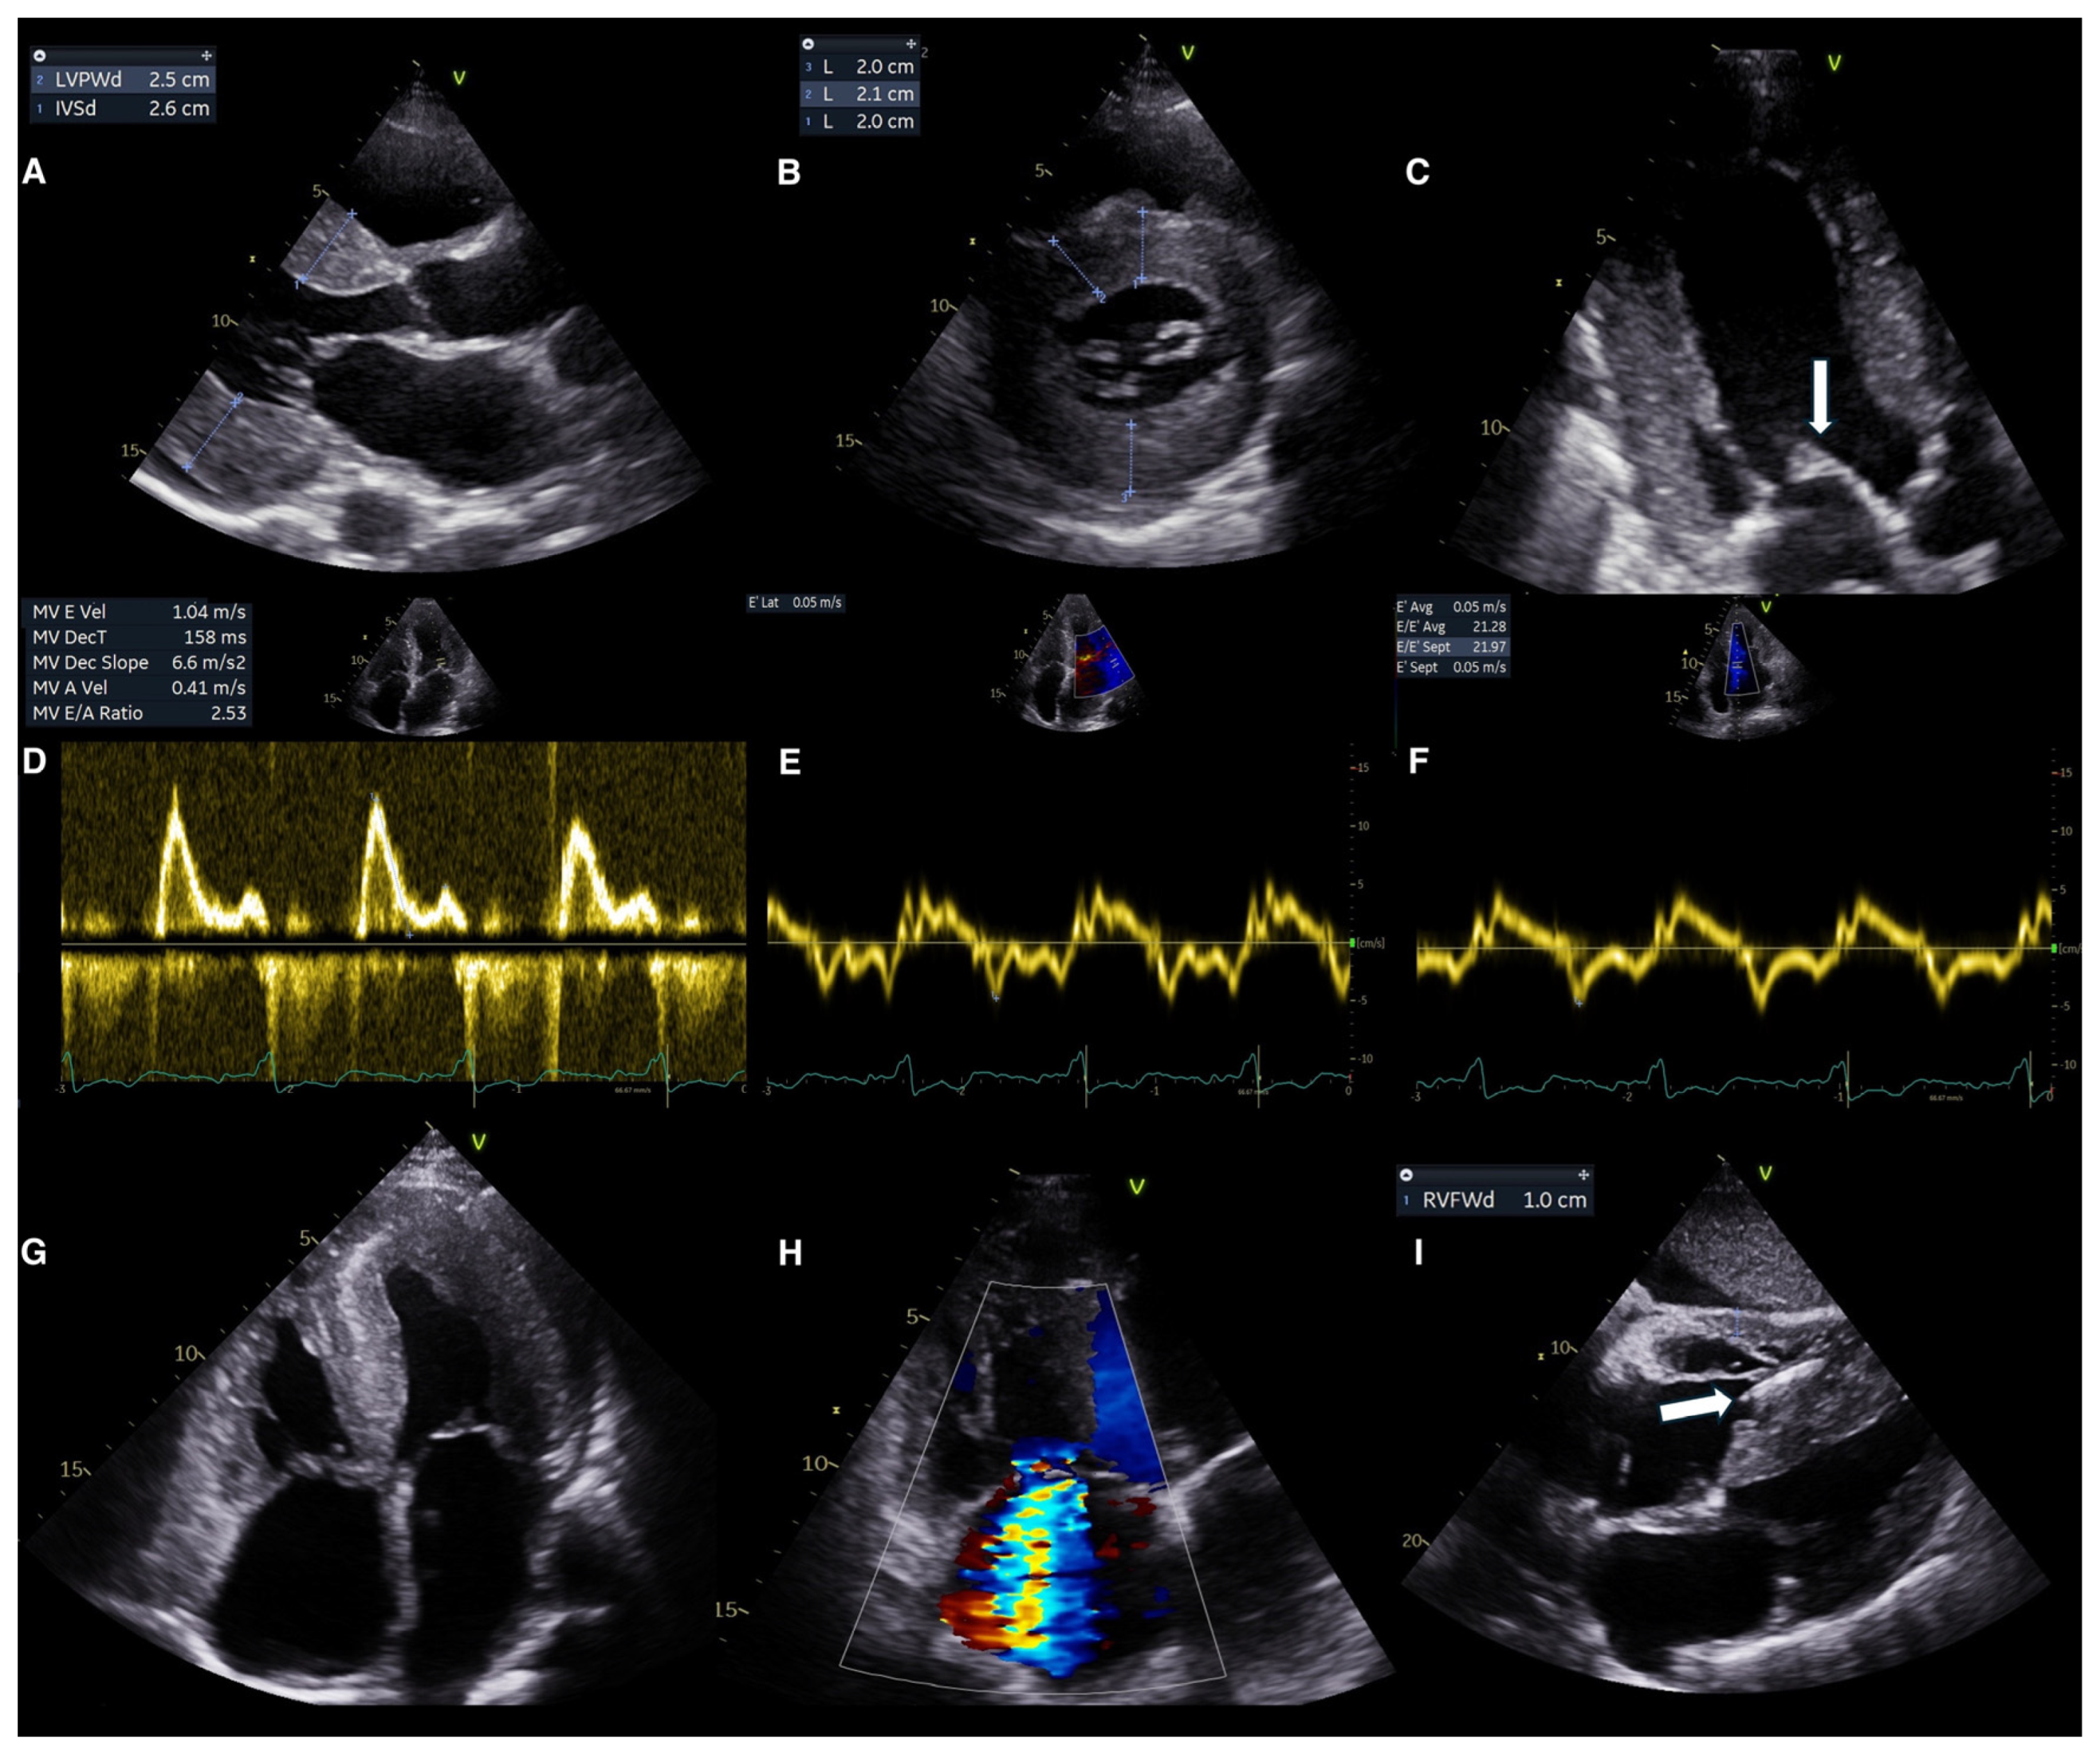

6.1. Echocardiography for Diagnosis

Conventional Echocardiography

6.2. Advanced Echocardiography

- Cuddy, S.A.M.; Chetrit, M.; Jankowski, M.; Desai, M.; Falk, R.H.; Weiner, R.B.; Klein, A.L.; Phelan, D.; Grogan, M. Practical Points for Echocardiography in Cardiac Amyloidosis. J. Am. Soc. Echocardiogr. 2022, 35, A31–A40. [Google Scholar] [CrossRef]

- Polo, J.M.; Barrenechea, A.R.U.; Martí, P.R.; Palacios, R.P.; Gutiérrez, A.G.; Juana, E.B.; Gracia, A.A.; Ayala, S.A.; Arregui, M.Á.A. Echocardiographic Markers of Cardiac Amyloidosis in Patients with Heart Failure and Left Ventricular Hypertrophy. Cardiol. J. 2023, 30, 266–275. [Google Scholar] [CrossRef]

- Licordari, R.; Minutoli, F.; Recupero, A.; Campisi, M.; Donato, R.; Mazzeo, A.; Dattilo, G.; Baldari, S.; Vita, G.; Zito, C.; et al. Early Impairment of Right Ventricular Morphology and Function in Transthyretin-Related Cardiac Amyloidosis. J. Cardiovasc. Echogr. 2021, 31, 17–22. [Google Scholar] [CrossRef]

- Bodez, D.; Ternacle, J.; Guellich, A.; Galat, A.; Lim, P.; Radu, C.; Guendouz, S.; Bergoend, E.; Couetil, J.P.; Hittinger, L.; et al. Prognostic Value of Right Ventricular Systolic Function in Cardiac Amyloidosis. Amyloid 2016, 23, 158–167. [Google Scholar] [CrossRef]